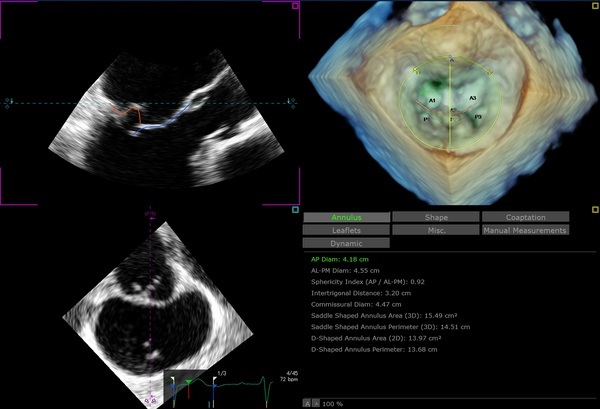

3D Auto MV

僧帽弁のLive 3Dボリュームを取り込み、収縮期全体における弁および周辺構造の動的な定性/定量データを提供します。